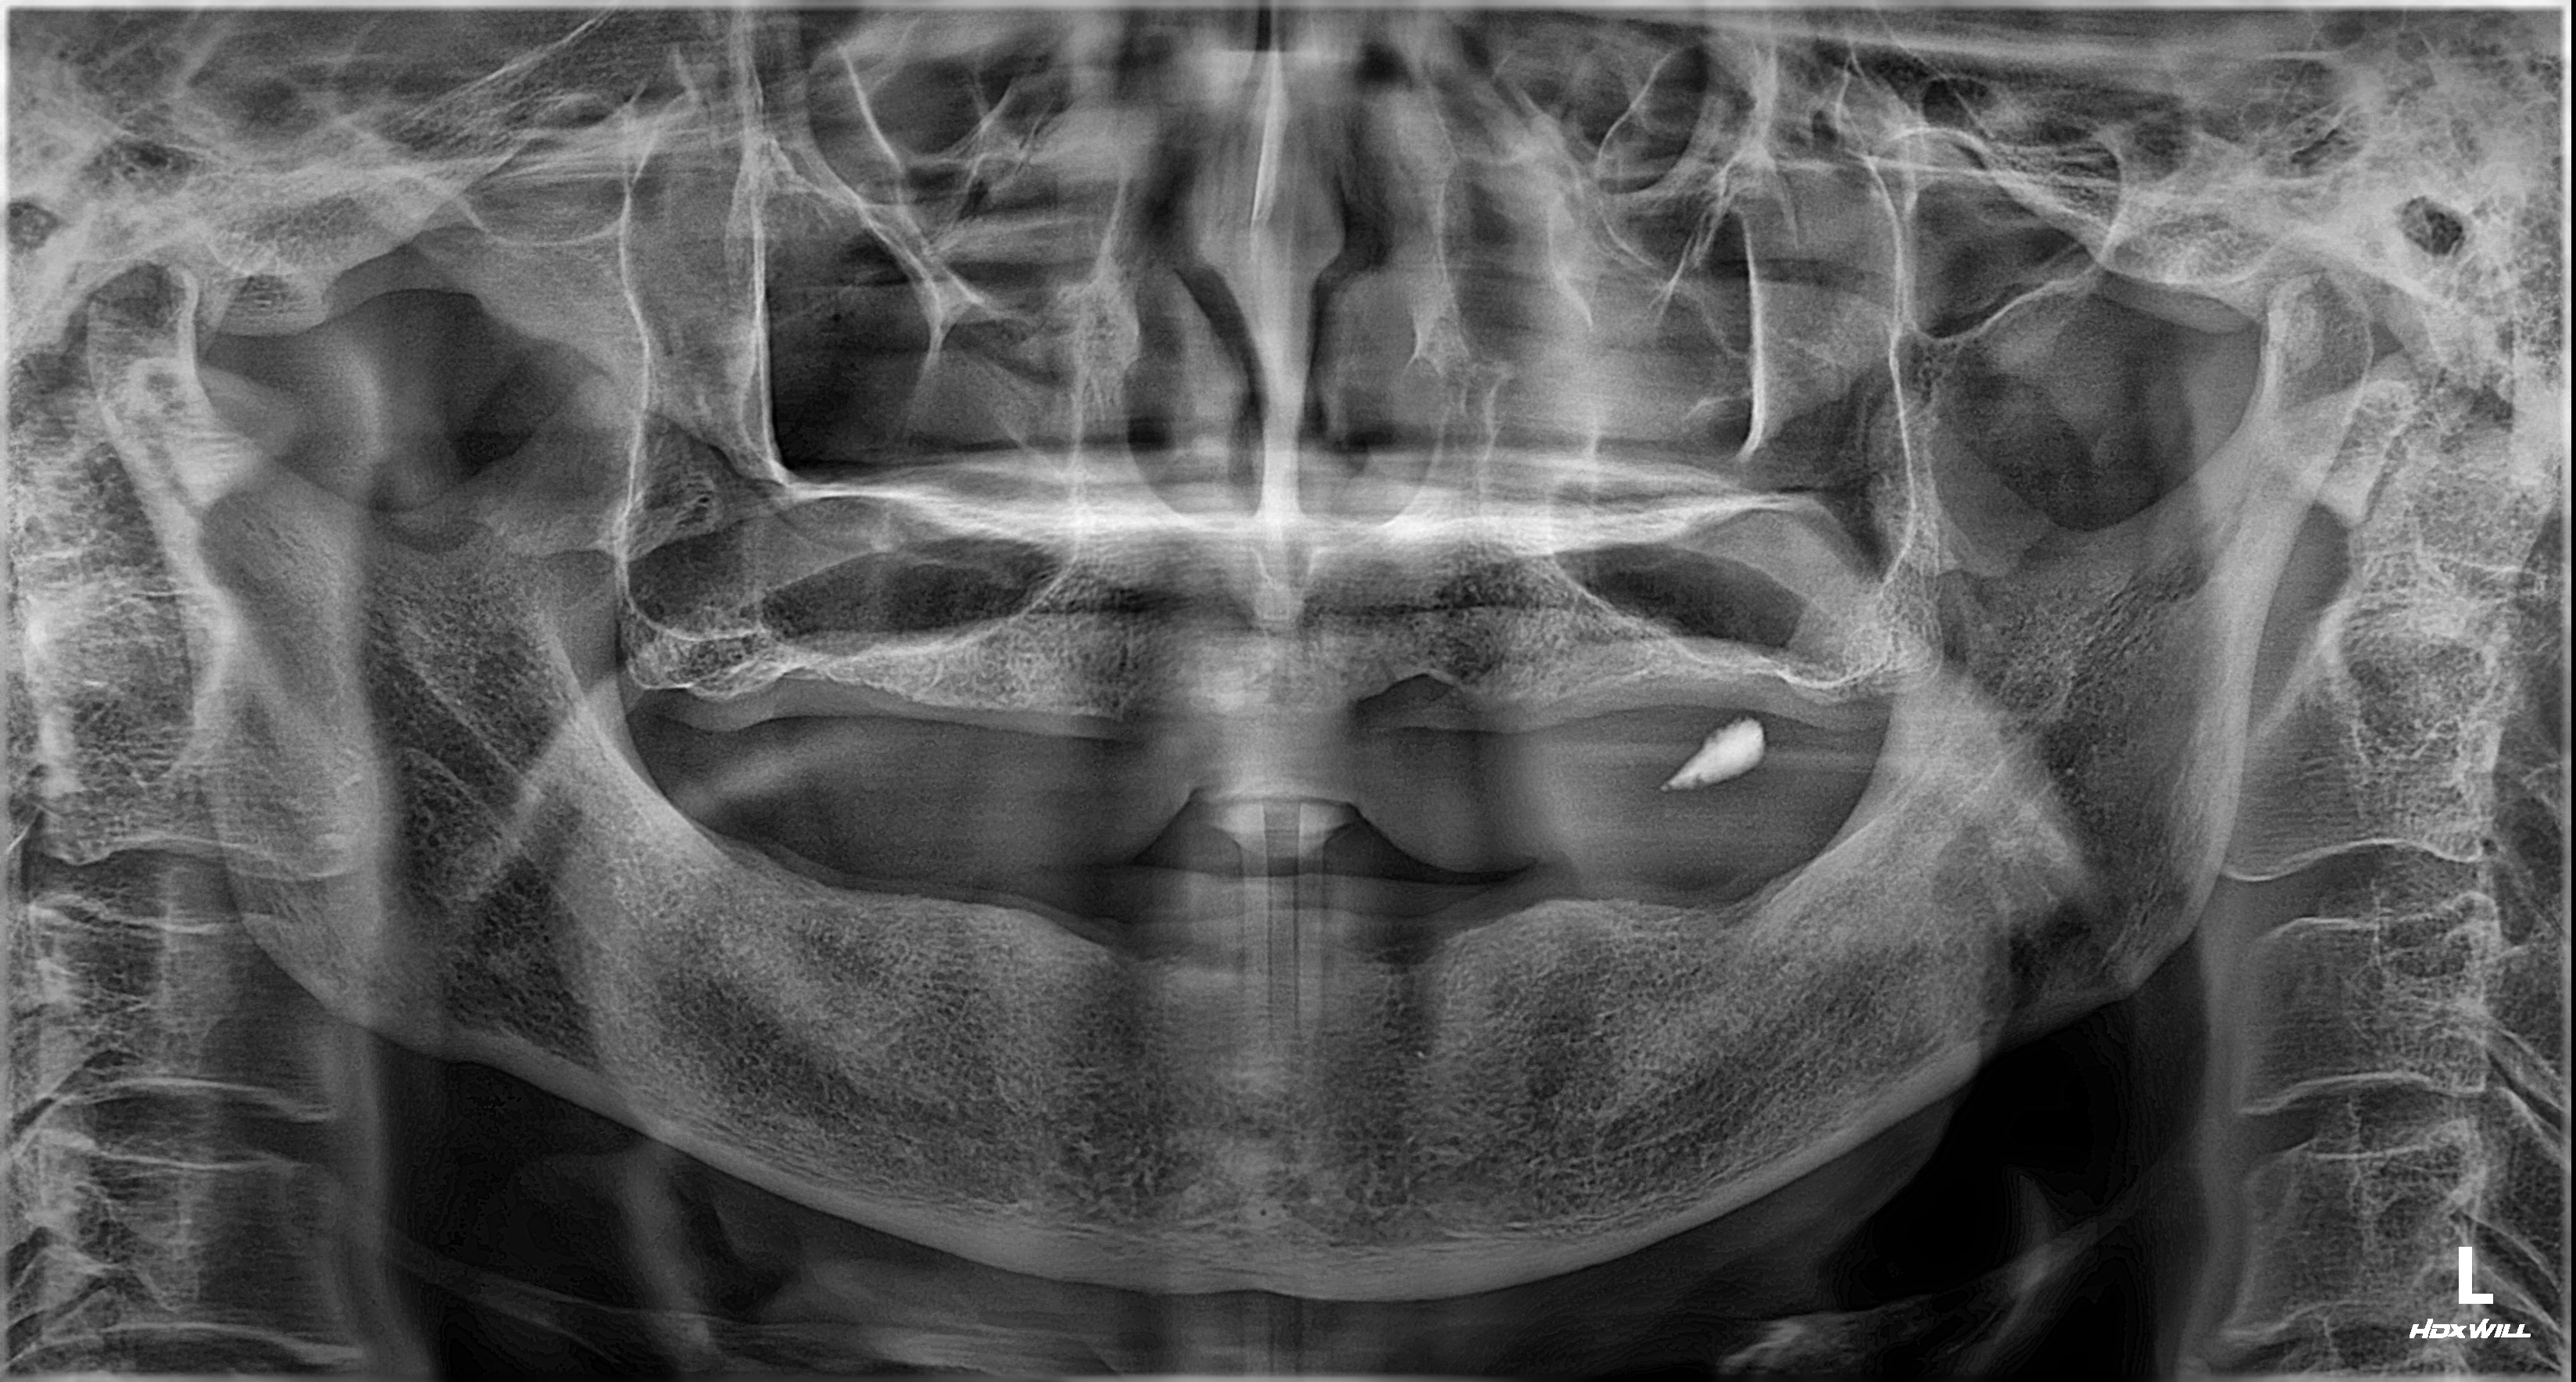

위 사진은 본원에서 진료받은 환자분의 동의하에 게재된 실제 사례입니다.

정확한 진단이 성공적인 수술의 시작입니다.